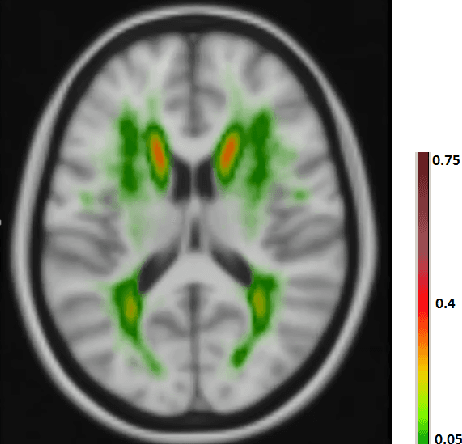

Abstract:The anatomical location of imaging features is of crucial importance for accurate diagnosis in many medical tasks. Convolutional neural networks (CNN) have had huge successes in computer vision, but they lack the natural ability to incorporate the anatomical location in their decision making process, hindering success in some medical image analysis tasks. In this paper, to integrate the anatomical location information into the network, we propose several deep CNN architectures that consider multi-scale patches or take explicit location features while training. We apply and compare the proposed architectures for segmentation of white matter hyperintensities in brain MR images on a large dataset. As a result, we observe that the CNNs that incorporate location information substantially outperform a conventional segmentation method with hand-crafted features as well as CNNs that do not integrate location information. On a test set of 46 scans, the best configuration of our networks obtained a Dice score of 0.791, compared to 0.797 for an independent human observer. Performance levels of the machine and the independent human observer were not statistically significantly different (p-value=0.17).